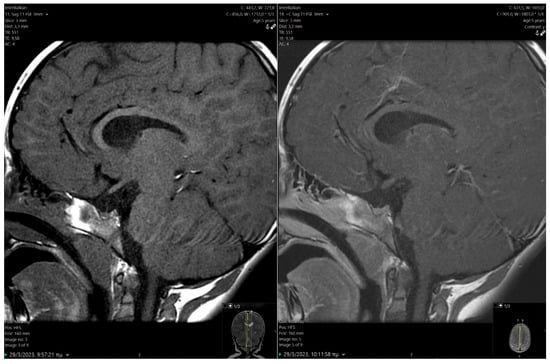

Given the GH deficiency (GHD), a magnetic resonance imaging (MRI) of the pituitary was performed, revealing a hypoplastic anterior pituitary lobe (height 2.8 mm), marked thinning of the pituitary stalk, and heightened signal intensity in the posterior pituitary gland (Figure 2), all indicative of Pituitary Stalk Interruption Syndrome (PSIS). Before initiating recombinant human GH (rhGH) treatment, the boy experienced a severe episode of hypoglycemia while suffering from gastroenteritis (glucose: 28 mg/dL), necessitating hospitalization. His cortisol level during that time was 34 μg/dL. The episode was successfully managed with intravenous glucose administration.

PSIS consists of an orphan syndrome involving the congenital abnormality of the pituitary gland, with three main characteristics: (i) the hypoplastic or inexistent anterior pituitary gland, (ii) absent or thin infundibulum, and (iii) ectopic posterior pituitary location. PSIS is presented during the first decade of life [40]. Several studies have attempted to explain the mechanisms that induce the triad of anomalies in PSIS. Two primary hypotheses posited for these abnormalities involve traumatic birth injuries (breech delivery, cesarean section, perinatal hypoxemia) and disturbances in the embryonic development of the hypothalamic–pituitary axis [41,42,43], none of which was applicable in the present case. Identifying familial instances of PSIS and the co-occurrence of central nervous system (CNS) malformations suggest a potential genetic origin, prompting molecular studies aimed at identifying responsible gene mutations [41,42,43]. However, the family history was unremarkable. Midline CNS malformations infrequently associated with PSIS involve optic nerve hypoplasia, absent septum pellucidum, and Chiari malformation [41,42,43,44]. Additional anomalies include micropenis and cryptorchidism [11], the latter being surgically corrected in our case.

Figure 2. Pre and post contrast sagittal T1-weighted images (MRI) showing hypoplastic anterior pituitary gland and thin infundibulum. Posterior pituitary bright spot is absent in normal position at pituitary fossa, features are most consistent with Pituitary Stalk Interruption. MRI: magnetic resonance imaging.